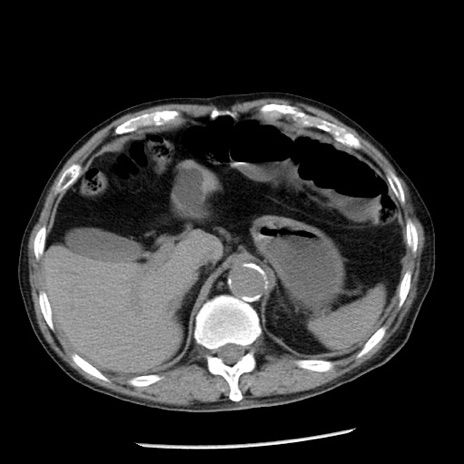

冠状断像

症例26(横断像)

【症例】80歳代男性

【主訴】嘔吐

【現病歴】昨晩2回嘔吐あり、今朝になっても嘔吐あり。来院。

【既往歴】胃潰瘍

【身体所見】意識清明、BT 37.6℃、BP 166/95mmHg、HR 100bpm、SpO2 97%、腹部:平坦・軟、腸蠕動音聴取良好、圧痛なし。

【データ】WBC 21900、CRP 1.46